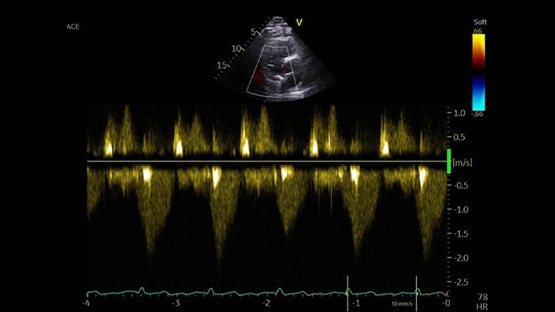

Cardio-online vous propose des vidéos d’experts sur des questions récurrentes liées aux valves aortique, mitrale et tricuspide, ainsi que des décryptages sur des sujets majeurs tels que le remplacement ou la réparation mitrale percutanée, l’alignement commissural, la sténose aortique, ou encore les fuites mitrale et tricuspide.